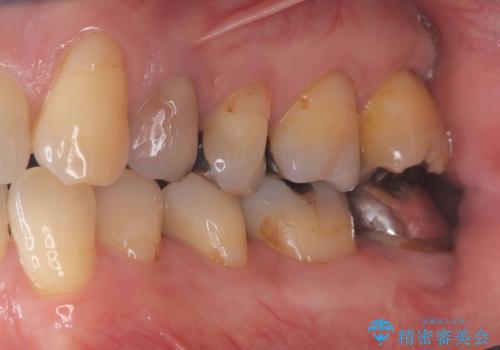

検査の結果、左下7番は歯周ポケットが8mmと深く、レントゲンでも根尖部から骨が溶けている状態が確認されました。エンドペリオ病変と診断し、精密根管治療による保存か、抜歯をしてインプラントで治療するかをご提案したところ、患者様は抜歯・インプラント治療を希望されました。

また、左下6番は銀歯と虫歯を除去した後、見た目や適合性に優れたオールセラミッククラウンで修復を行いました。

インプラントとセラミック治療を組み合わせることで、見た目も自然で噛み心地の良い状態を回復することができ、患者様にも大変ご満足いただけました。